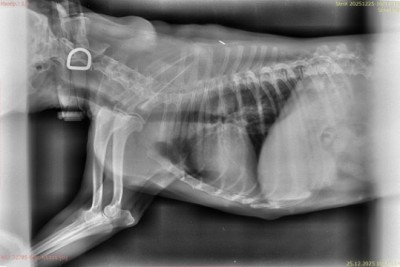

Изображение